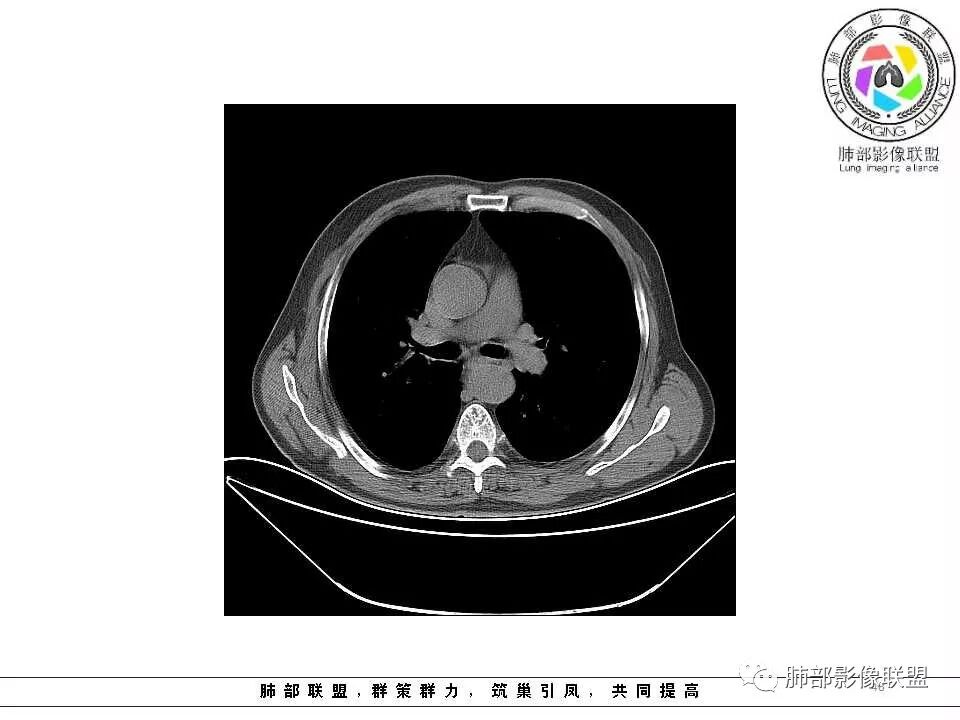

老年男性,两肺可见小叶中央型肺气肿,提示应该有抽烟史。2016年片,右肺门支气管稍模糊,考虑慢性感染,纵膈淋巴结稍大。但2017年左肺上叶新发占位,堵塞支气管,引起局部肺不张伴感染,且纵膈淋巴结较2016年变大,患者同时伴有咯血,考虑恶性。鳞癌?类癌?小细胞?

肺气肿背景,2016年左肺上叶上舌段见微结节,2017年5月左肺结节增大,密度均匀,边缘光滑锐利,与邻近血管关系密切,血管贴壁走行,外侧见尖状突起,下舌段片状影,沿着支气管走行,内有粘液栓,考虑鳞癌,鉴别小细胞肺癌。

肺气肿背景,2016年左肺上叶上舌段见微结节,一年后左肺结节增大,密度均匀,边缘光滑、膨隆,似见小分叶,下舌段片状影,沿着支气管走行,内,老年患者,咯血1月。考虑恶性病变并阻塞性肺炎,鳞癌?注意鉴别结核。

老年男性,咯血1月,肺气肿背景,16年左肺上叶舌段结节,左肺门疑似淋巴结肿大,呈结节感。17年左肺上叶舌段见沿支气管走行分布结节 远端阻塞性肺炎,左肺门淋巴结肿大明显,首先考虑恶性病变,鳞癌?类癌?

老年男性,肺气肿背景,左肺上叶舌段一年前小结节后长大,实性,与邻近气管关系密切,远端有少许小片状炎症类小结节状,左肺门淋巴结肿大,首先考虑恶性,鳞癌可能性大,代排小细胞癌。病灶下方斑片状影,考虑炎症。

老年男性,肺气肿背景,对比前片,左肺上叶舌段结节较前进展,周围有斑片状条状密度增高影,左肺门淋巴结肿大,有咯血史抗炎后效果不佳,目测增强强化不好判断,考虑肺癌并阻塞性肺炎可能,鉴别炎症性肺癌,真菌类肺炎,肺脓肿,肺结核,建议完善肿瘤标志物,结核相关检查,病原体检查。